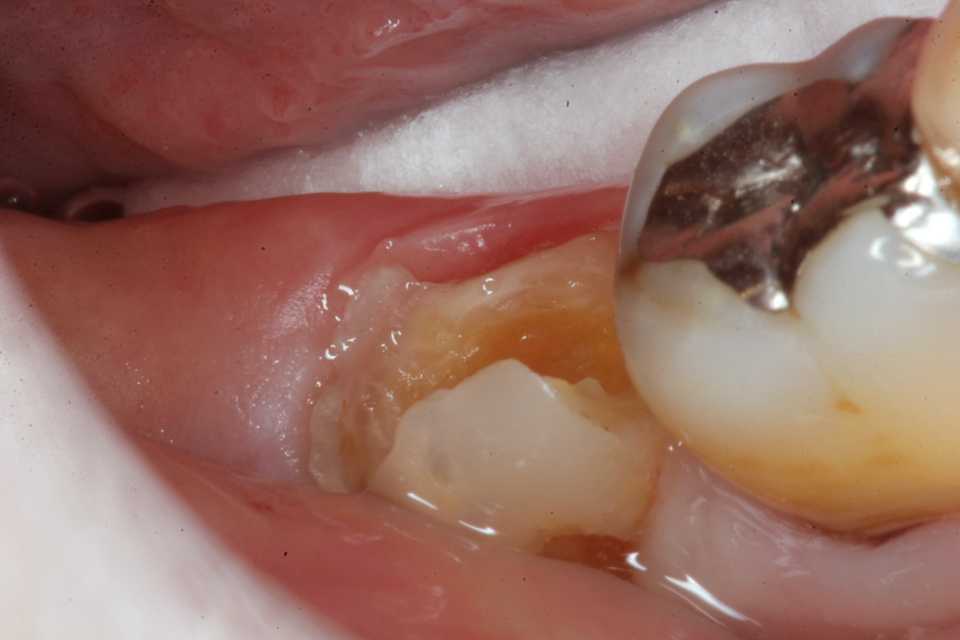

ストリップスを使わない隣接面CR(ダイレ… 2025.11.26

ストリップスを使わない隣接面CR(ダイレ… 2025.11.07